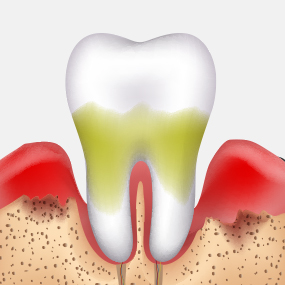

인체에 유해한 금속 성분을 사용하지 않으며,

환자의 구강 상태와 치료 목적을 면밀히 고려해

장기적으로 안전하고 기능적인 보철물만을 선택합니다.

PFM 크라운

내부 금속 + 외부 도자기 구조, 강도는 좋지만 잇몸 변색 우려 있음